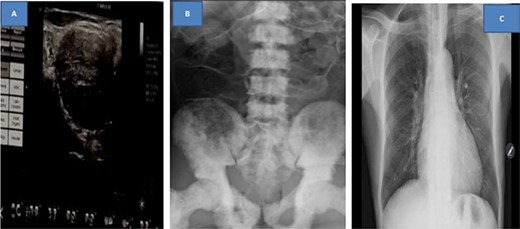

Abdominal pelvic ultrasound showed right moderate hydronephrosis with multiple pelvic masses that were separate from heterogeneous prostatomegaly (Fig. 1A). Kidney, ureter and bladder (KUB) X-ray revealed multiple osteoblastic lesions on the iliac wings and lumbar vertebrae (Fig. 1B); however, chest X-ray was normal (Fig. 1C). Abdominopelvis computed tomography scan was ordered but due to financial constraints, the patient was unable to afford, thus the staging was done by combination of the clinical presentation of the patient; (T3) as the prostate capsule was hard with an extra-capsular extension; (N3) due to the presence of supraclavicular lymph node involvement and (M1a) for the presence of osteoblastic lesions on the bone from the X-ray (Fig. 1C).

Ultrasound showing pelvic masses (A), kidney, ureter and urinary bladder X-ray showing osteoblastic lesions (B), and normal chest X-ray (C)